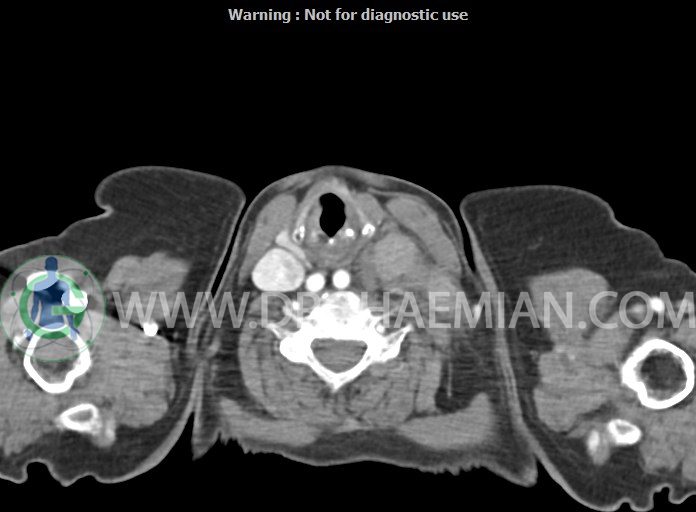

در سی تی اسکن اسپیرال از گردن با تزریق (مولتی دیدکتور 16 با مقاطع ظریف و بازسازی های ساژیتال و کرونال):

– تصویر توه های نسج نرمی oval shape متعدد با Enhancement تقریباً هوموژن، قرار گرفته در سمت چپ گردن، در لول غضروف کریکوئید با اثر فشاری شدید و compression ورید ژوگولار، با گسترش تحتانی به اینفراکلاویکولار چپ، به حداکثر ابعاد 28x50mm (با Enhancement مختصر هتروژن در این توده)

در درجه اول مطرح کننده لنفادنوپاتی متاستاتیک مطرح می باشد بالین، تومورهای منشأ گرفته از غلاف عصبی زنحیره سمپاتیک چپ گردنی، شبکه براکیال و لنفوم نیز در DDX قرار دارند. لذا نمونه برداری بافتی جهت بررسی بیشتر توصیه می شود.

– اسکولیوز مهره های سرویکال با تحدب به راست، احتمالاً در زمینه اثر فشاری توده های مذکور

مشهود است.